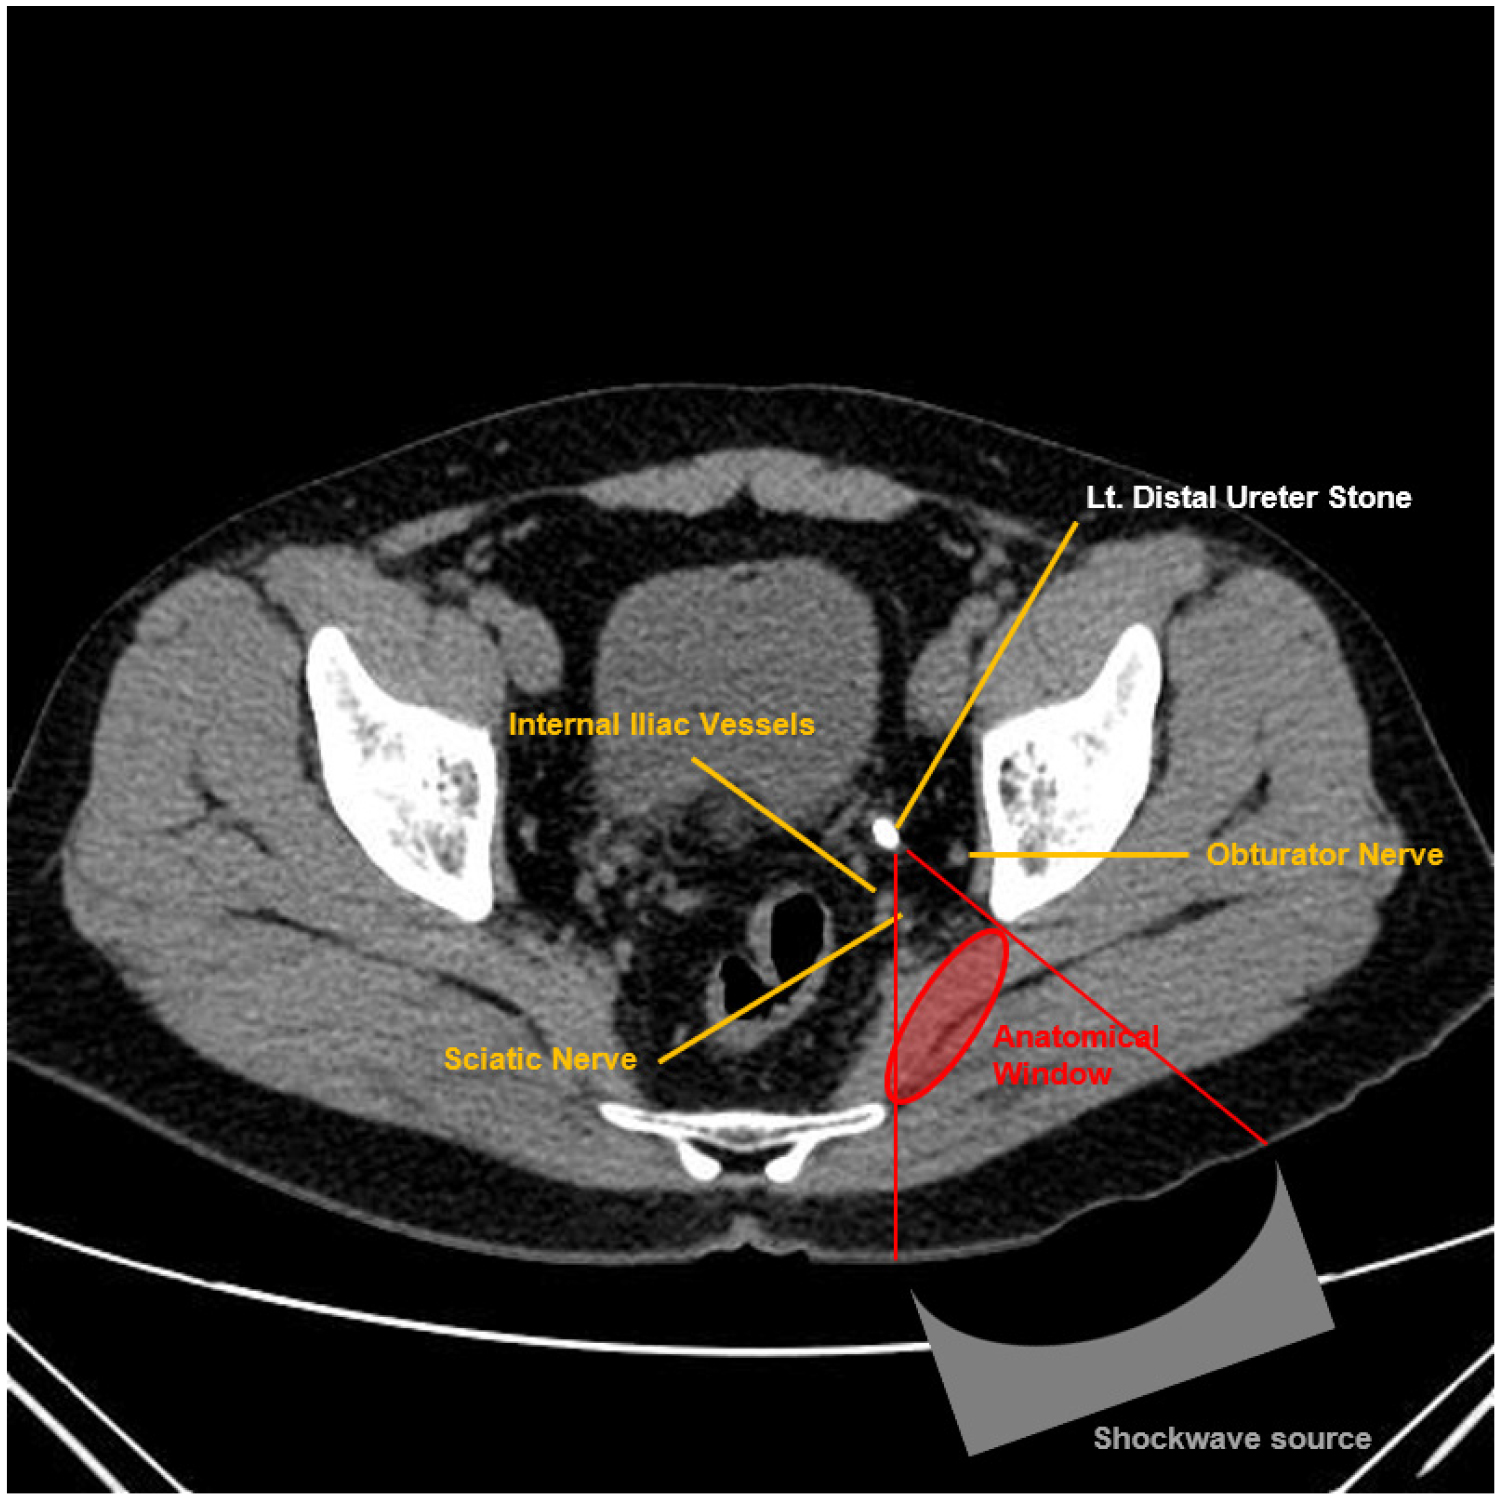

앙와위를 이용한 경둔근 접근법의 가장 우려되는 합병증은 좌골신경 손상이다. 하지만 Choo 등의 연구에서는 참여한 환자들 중 좌골 신경 손상의 전형적인 증상인 하지의 쇠약이나 저림, 무감각 또는 발처짐 등을 호소한 환자는 없었다 [12]. 다른 연구에 따르면 충격파를 전달하는 각도가 중요하여, 환자가 통증을 호소할 때 치료 각도를 조금 조정하면 좌골 신경 손상의 위험을 완화할 수 있다고 보고하였다 [16], [그림 2].

경둔근 접근법으로 치료를 받은 환자는 앙와위로 누운 상태에서, 충격파 발전기는 수직축에 대해 40° 각도로 고정한 후 환자의 엉덩이에 밀착시켜 체외충격파 치료를 받는다. 머리와 다리는 환자의 편안함을 위해 베개로 받쳐 준다 [12], [그림 3].

하부요관결석 환자에서 앙와위를 통한 경둔근 접근법 체외충격파쇄석술은 안전하고 효과적인 방법으로 알려져 있다. 앙와위에서 충격파 발전기를 수직방향에서 40° 각도로 유지하여 엉덩이에 밀착시켜 시행하는 방법으로, 대둔근을 통해 대좌골공으로 충격파를 전달하여 감쇄를 최소화한다. 또한 장을 통하지 않기 때문에 장천공 같은 심각한 합병증의 위험이 거의 없다. 그리고 편안히 누운 자세에서 시행하기 때문에 전통적인 복와위 방법에 비해 불편감을 덜 느끼게 되고 환자들의 만족감 또한 높은 것으로 보고되고 있다. 특히 비만하거나 고령인 환자에서 적극적으로 고려할 수 있는 시술 방법이다.